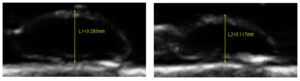

Fifty human lens nuclei were collected from extracapsular cataract extraction (ECCE) surgeries. Each lens was subjected to a controlled compressive load (0.2 N), and deformation was recorded using ultrasound imaging to calculate Young’s modulus as the ground-truth stiffness measure. Preoperative features included age, gender, cataract grade, lens diameter, diabetes status, and aspirin use—all routinely available in clinical settings.